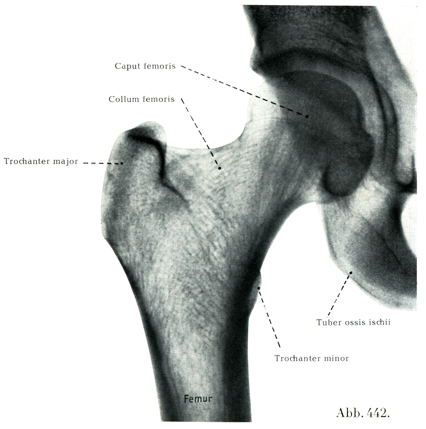

[図442] 股関節 生体の右股関節のレントゲン写真,腹背照射(7/10)

この関節をつくっている骨は寛骨と大腿骨である.

関節面は大腿骨頭Caput femorisと月状面Facies lunataおよびそれを補う寛骨臼横靱帯Lig. transversum acetabuliと関節唇Labium articulareである.

大腿骨頭の関節面は球面のほぼ2/3を占める.曲率半径は男で2.6cm,女で2.4cmである(Fick).従って関節頭の弯曲は正確に関節窩の弯曲に一致しているわけである.(球形からそれている場合がある.)軟骨の厚さは関節頭の中央から縁へかけて次第に減じる(これについてはWernerの詳細な報告がある).大腿骨頭窩は軟骨の上縁より下縁に近くあって,大腿骨頭靱帯がここに付いている(図441).